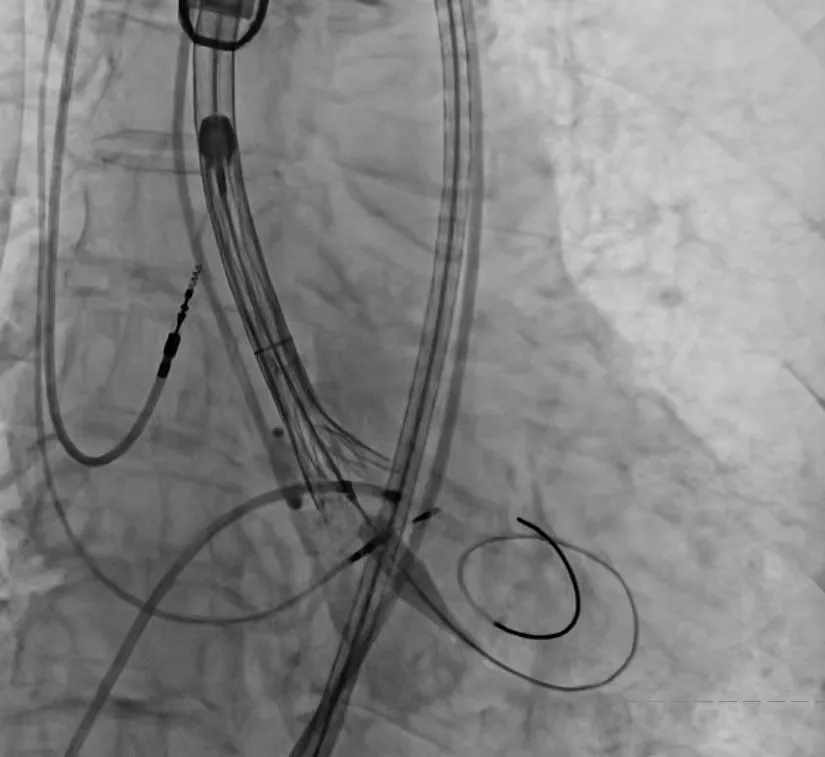

▶ 创新技术保障安全:采用"预扩张球囊分级扩张"策略,并应用冠脉保护技术和循环快速起搏,最大限度降低手术风险。

手术过程严谨有序:经术前精准评估与周密准备,团队成功送入预先装载的自膨式支架瓣膜输送系统,顺利完成过弓、跨瓣操作;经造影定位后,在180bpm快速起搏下精准释放瓣膜。瓣膜释放后,术中实时超声显示根部瓣架形态良好、启闭正常,瓣叶中心及瓣周未见反流;造影显示瓣膜位置满意、形态良好,冠脉显影清晰,入路血管无损伤,历经90分钟后,手术圆满成功。

术中影像